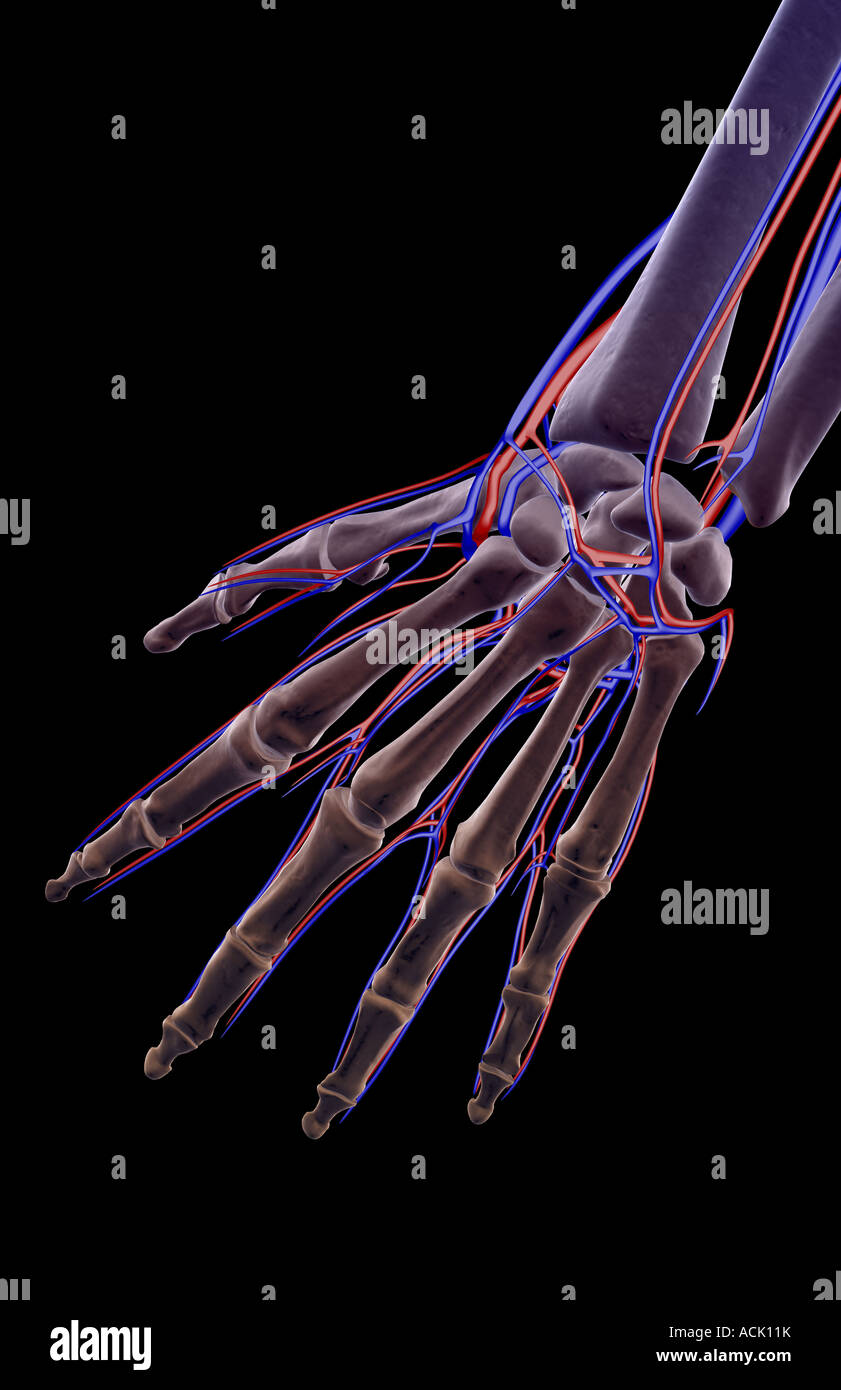

The blood supply of the hand Stock Photohttps://www.alamy.com/image-license-details/?v=1https://www.alamy.com/stock-photo-the-blood-supply-of-the-hand-13174686.html

The blood supply of the hand Stock Photohttps://www.alamy.com/image-license-details/?v=1https://www.alamy.com/stock-photo-the-blood-supply-of-the-hand-13174686.htmlRFACK11K–The blood supply of the hand